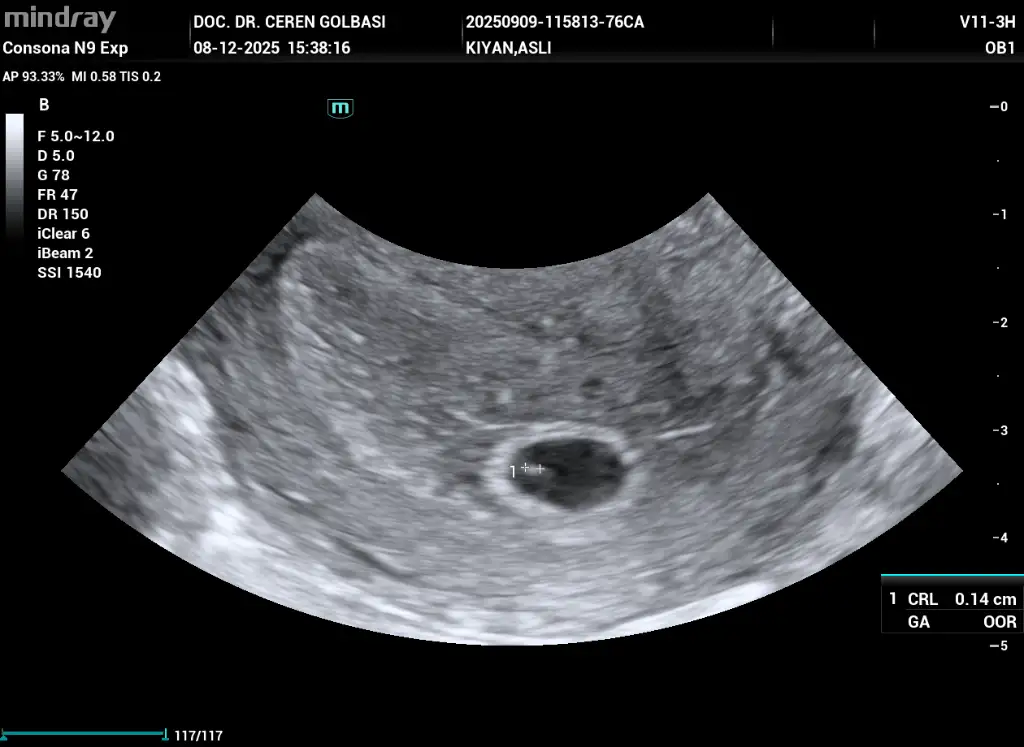

Bugün doktora gittim son adet tarihim 26 ekimdi bebeği göremedik 5+4 olarak söyledi şu anki durumumu benimle aynı olan var mı acaba birde kistim varmış çok ağrı yapıyor kist geçer değil mi

• _QRCodeSendTask_20251208154216_QR_1_202512081538090102OB.webp

_QRCodeSendTask_20251208154216_QR_1_202512081538090102OB.webp

36,2 KB · Görüntüleme: 3